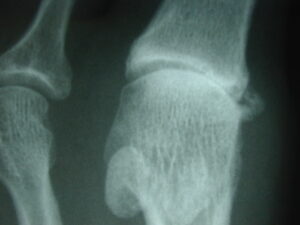

Gout is a frequently mentioned disease in historical texts including the bible. Gouty arthritis is caused by a build up of uric acid crystals in the fluid of the joint spaces and tissues throughout the body. Uric acid is a breakdown product that forms after the body digests and metabolizes the food s we eat. Some people inherit an abnormality in the body’s ability to process uric acid. The inability by the body to handle uric acid will lead to painful gouty attacks in the joints and elsewhere in the body.

Gouty arthritis results in an extremely painful attack with a rapid onset of joint inflammation. The joint becomes very hot, very red and very painful to any pressure including light touch. The big toe joint is one of the most common areas in the foot affected by gouty arthritis.

Over time, the attacks of gout typically occur more frequently. Therefore, gout can become a chronic recurrent problem. Chronic gout can also cause hard lumps of uric acid deposits in the tissues. This can cause joint destruction to occur.